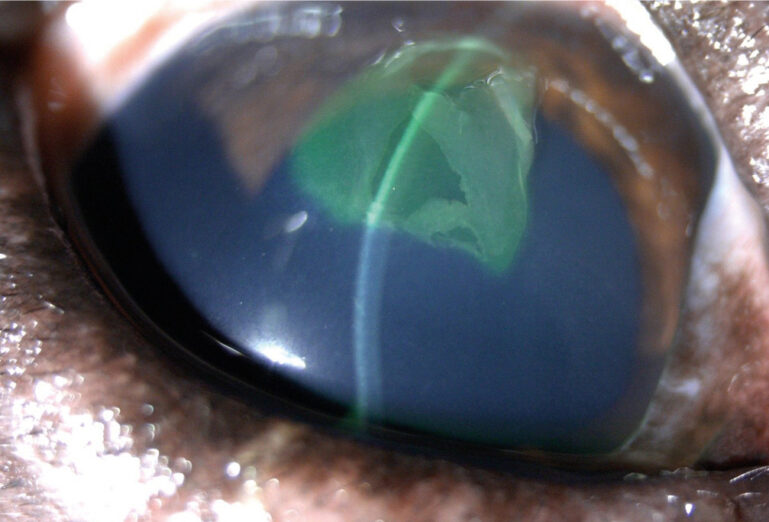

- Úlceras complejas (imagen 2): afectan al estroma corneal, no cicatrizan en menos de 7 días. Pueden tener factores de complicación como queratomalacia o infiltrado celular.

Imagen 2. Úlceras complicadas. A) Estromal anterior asociada a infiltrado celular. Nótese el edema corneal difuso. Imagen 2. Úlceras complicadas. B) Estromal profunda predescemética asociada a neovascularización crónica. Imagen 2. Úlceras complicadas. C) Estromal profunda con queratomalacia.